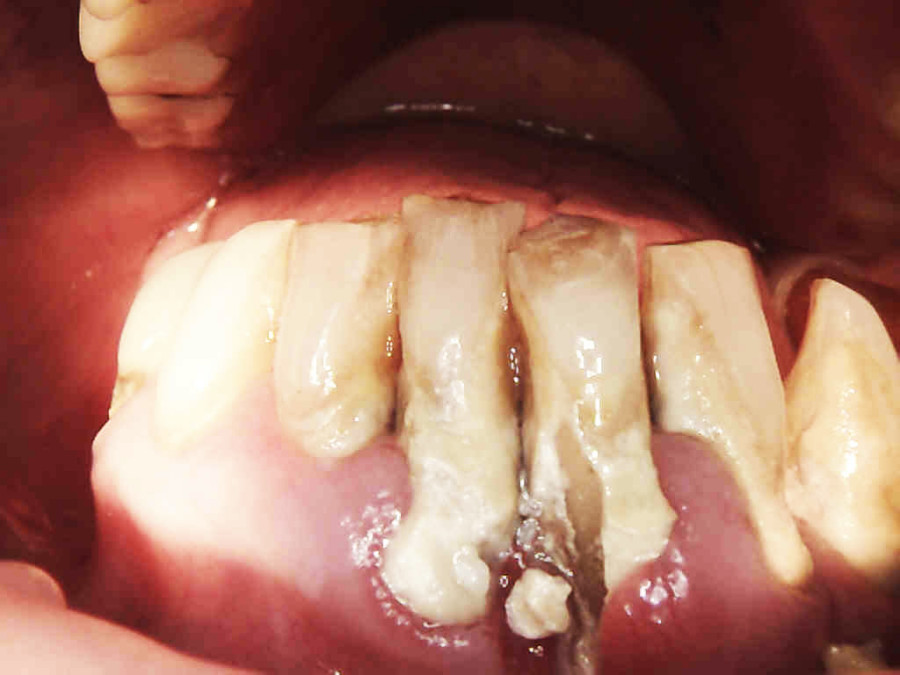

Postępowanie rozdzielono na dwie wizyty. Badaniem klinicznym, oceniając wskaźniki periodontologiczne, uzyskano wartości API 100%, PBI 100% świadczące o konieczności poprawy higieny i procesie zapalnym dziąseł, duże złogi kamienia nad i poddziąsłowego, bardzo obfity biofilm, pogłębione wszystkie kieszonki dziąsłowe, ciężkie zapalenie dziąseł, ruchomości zębów dolnych III stopnia, duży zanik kości. Badanie kliniczne błony śluzowej jamy ustnej nie wykazało zmian patologicznych.

Na drugiej wizycie przeprowadzono dokładną kontrolę pozabiegową. Oznaczono ponownie wszystkie wskaźniki notując znaczną poprawę – API 17%, PBI 33%, sprawdzono głębokość kieszonek i ruchomości zębów.

Płytkę bakteryjną stwierdzono tylko w jednęj przestrzeni, krwawienie w dwóch, niektóre kieszonki spłyciły się. Niestety pani odłożyły się nowe złogi kamienia przy zębach siecznych. Przeprowadzono dokładny instruktaż szczotkowania i nitkowania, dobrano dla pacjentki odpowiednie środki do codziennej higieny jamy ustnej: szczoteczki międzyzębowe , pasty, płukanki, nici oraz skierowano dalej do periodontologa w celu przeprowadzenia dokładnego badania głębokości kieszonek i ewentualnego zabiegu root planingu .